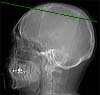

Radioanatomie TDM de l'encéphale

Sillon central (Rolando)

Gyrus pré central

Gyrus post central